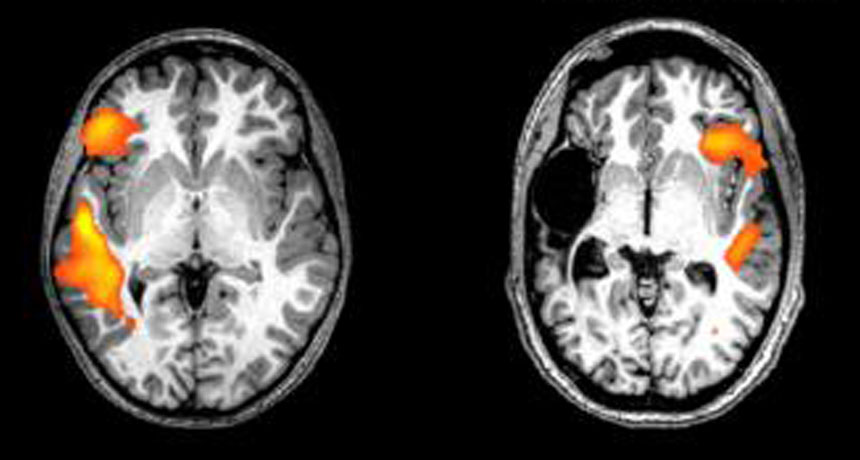

SWITCHING SIDES These fMRI scans show the brain activity of a healthy person (left) and a stroke patient (right) while doing a language-related task. Having a stroke just before or after being born flips key language-processing areas from the left to the right side of the brain, a new study shows.

E. NEWPORT